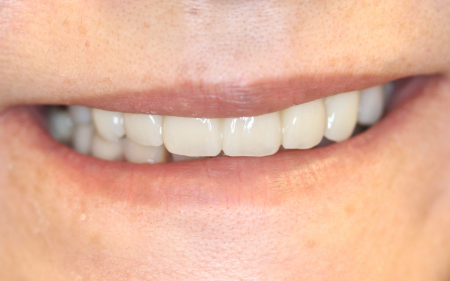

その後、上の歯すべてに仮歯である「プロビショナルクラウン」を作製し、噛み合わせや歯ぎしりをした際の歯の当たり具合などをしっかり確認して形を整えたあと、プロビショナルクラウンの形に応じて最終的な被せ物を装着しています。

被せ物については、口を開けた時に特に目立つ前歯6本(右上犬歯/3番~左上犬歯)は患者様と相談した結果、耐久性と審美性に優れた自費の被せ物「ジルコニアクラウン」を選択されています。

欠損していた左上奥歯(第2大臼歯/6番)には両隣の歯を土台にして橋渡しのように被せ物を入れる保険の「ブリッジ」がもともと入っていましたが、今回前歯同様、ジルコニアクラウンでやり替えを行いました。

最後に、左右上の歯2本(第1小臼歯/4番)は保険の白い被せ物「CAD/CAM冠」を、右上奥歯2本(第1大臼歯、第2大臼歯)も保険の金属製の被せ物をそれぞれ装着し、治療を終了しています。